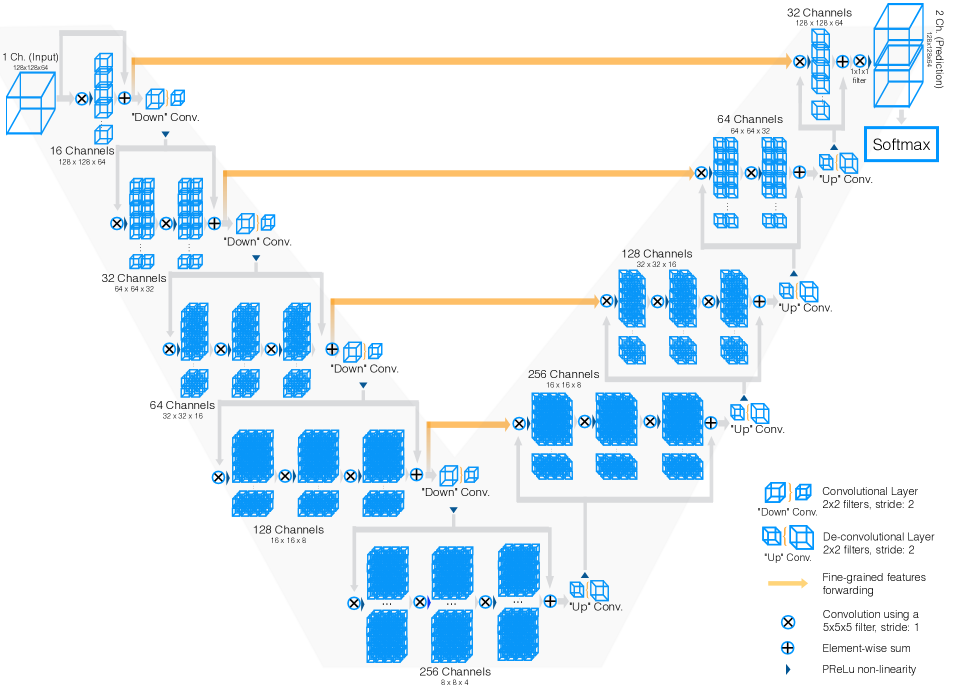

相对于二维语义分割,三维语义分割利用体素的三维结构信息来分割医学影像,具有更强的抓取空间信息的能力。因为三维分割利用了周围邻近切片及沿着z轴的轴向信息,具有更好的上下文信息,进一步提高了模型的泛化能力。此外,三维语义分割相较二维语义分割也有利于消除噪声和伪影的影响。当前使用的医疗影像数据具有较高的空间分辨率且为三维影像数据,因此使用三维语义分割模型进行分割通常是更适合的处理方式。这次使用的三维语义分割模型 VNet 采用了一种自下而上的方法,并且使用了 U 形连接搭建网络结构,以捕捉到影像数据的不同尺度的细节信息。由于相邻的体素往往具有密切的相关性,因此 VNet 引入了 3D 卷积、转置卷积操作以及残差 U 形连接来捕获和应用融合上下文信息,从而提高模型的精度和泛化能力。 分割医疗影像数据时,由于病变区域可能会占整个影像的很小一部分,导致标注数据的分布不均衡,VNet 提出 Dice 损失函数,来减少不平衡分布对模型训练的影响,使模型更加稳定。VNet 整体结构如下。